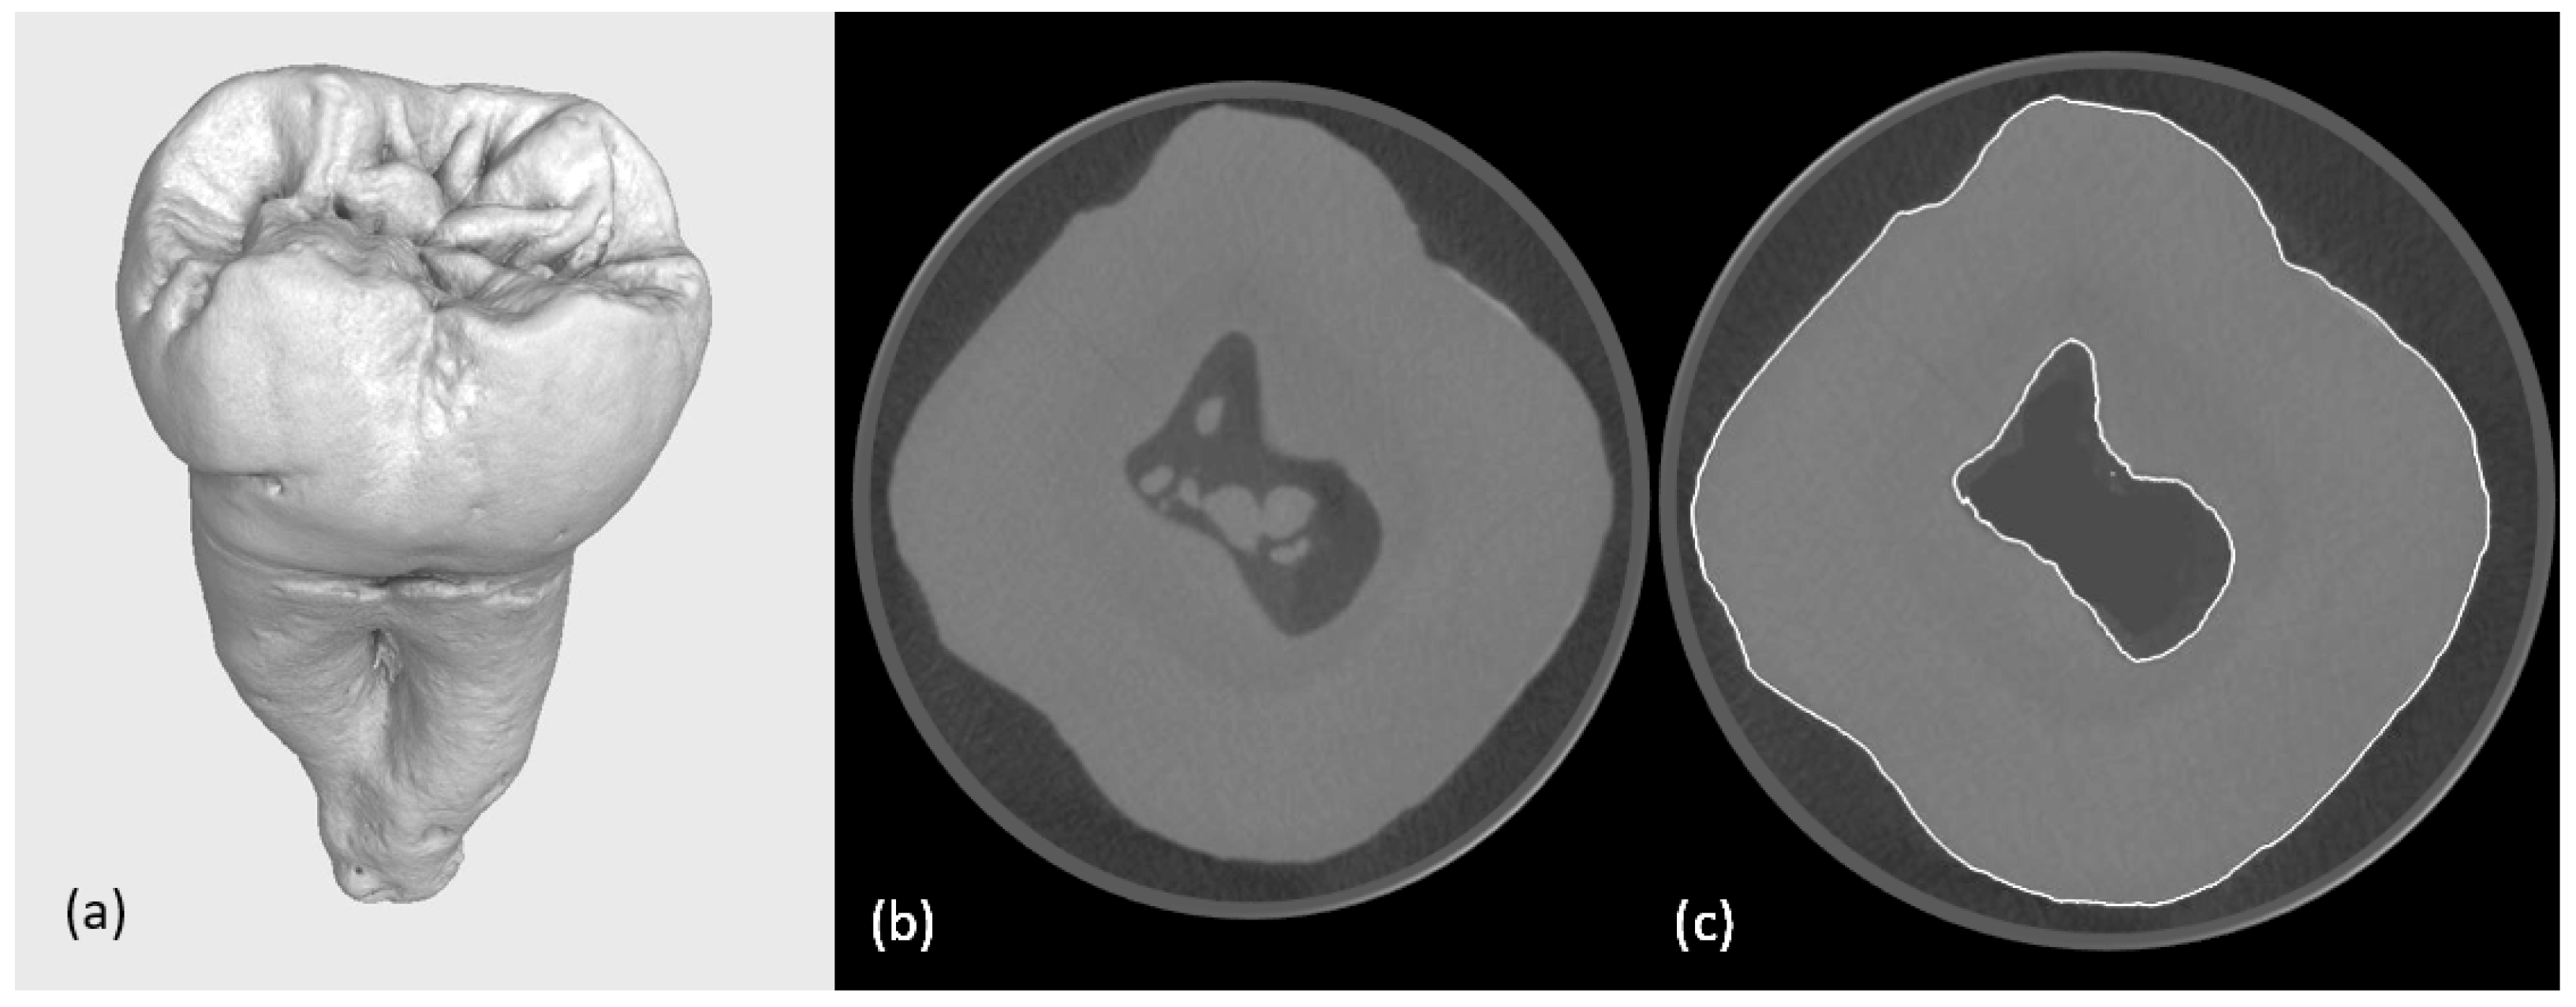

The high-resolution industrial micro-CT scanning of the extracted human molar provided detailed digital datasets with reduced quantum noise and beam-hardening artefacts. The analysis of the computed tomography data revealed multiple calcified structures within the pulp chamber and root canals (Figure 1). While anatomically accurate, these features increased model complexity and computational demands. Consequently, calcified regions were digitally segmented and removed, as they were not essential for the intended mechanical analysis. This masking was achieved using a region-growing algorithm and manual refinement with a digital pen, followed by a grey value interpolation to preserve anatomical continuity.

Figure 1. (a) A reconstruction of a second human molar; (b) slice from the micro-CT scanning calcifications are visible in the pulp chamber; (c) tooth with digital surface determination and digital removal of calcifications from the pulp chamber.